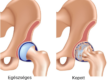

A porckopás megelőzésére, valamint a már meglévő porckopás kezelésére számos porcerősítő hatóanyag áll rendelkezésre, hogy segítse megőrizni vagy visszaállítani az ízületben található porcszövet megfelelő struktúráját, rugalmasságát, és egészségét. A következőkben szeretném a legfontosabbakat felsorolni.

A glükozamin csökkenti az ízületi fájdalmat és gyulladást a porclebontó és gyulladást okozó enzimek gátlása révén. Helyreállítja a porc alapanyagcseréjét, így alkalmazásával a károsodott ízületi porc fokozatosan regenerálódik és újraképződik. Fájdalomcsillapító és porcépítő hatása nem azonnal a szedés elkezdését követően alakul ki, hanem nagyjából kb. 2 hétre van szükség ahhoz, hogy érezhető porcépülés következzen be. Amennyiben egy kúrát végig szed, ami megközelítőleg 3 hónap, elvárhatja tőle hogy ugyanannyi ideig meg is maradjon a felépült porcmennyiség.

A porcerősítő kondroitin erős vízmegkötő képessége révén segít helyreállítani a porckopás során elvesztett rugalmasságot, víztelítettséget, így segíti a tápanyagok eljutását a porcsejtekhez, ami azért nagyon fontos, mert a porcnak nincs saját vérellátása, a tápanyagokhoz a porcsejtek csak a víztelített tereken keresztül tudnak hozzájutni. A szükséges alkotórészeket a porc az ízületben található ízületi folyadékból veszi fel. Ebben az esetben a vér az ízületi tokba viszi be a kondroitint és onnan kerül be az ízületi térbe.

A hialuronsav az ízületi folyadék egyik alapanyaga, vízmegkötő képességével segíti az ízületi folyadék viszkozitásának fenntartását. Porcerősítő hatása úgy nyilvánul meg, hogy az ízületben találkozó porcfelszínek között kenőanyagként működik, így megakadályozza, hogy a porcfelszínek egymáshoz dörzsölődjenek, megkopjanak. A kollagén porcerősítő hatását a felépítésének köszönheti, ugyanis a rugalmas rostok hálózatot alkotva teret biztosítanak a vízmegkötő kondroitinnak és glükozaminnak.